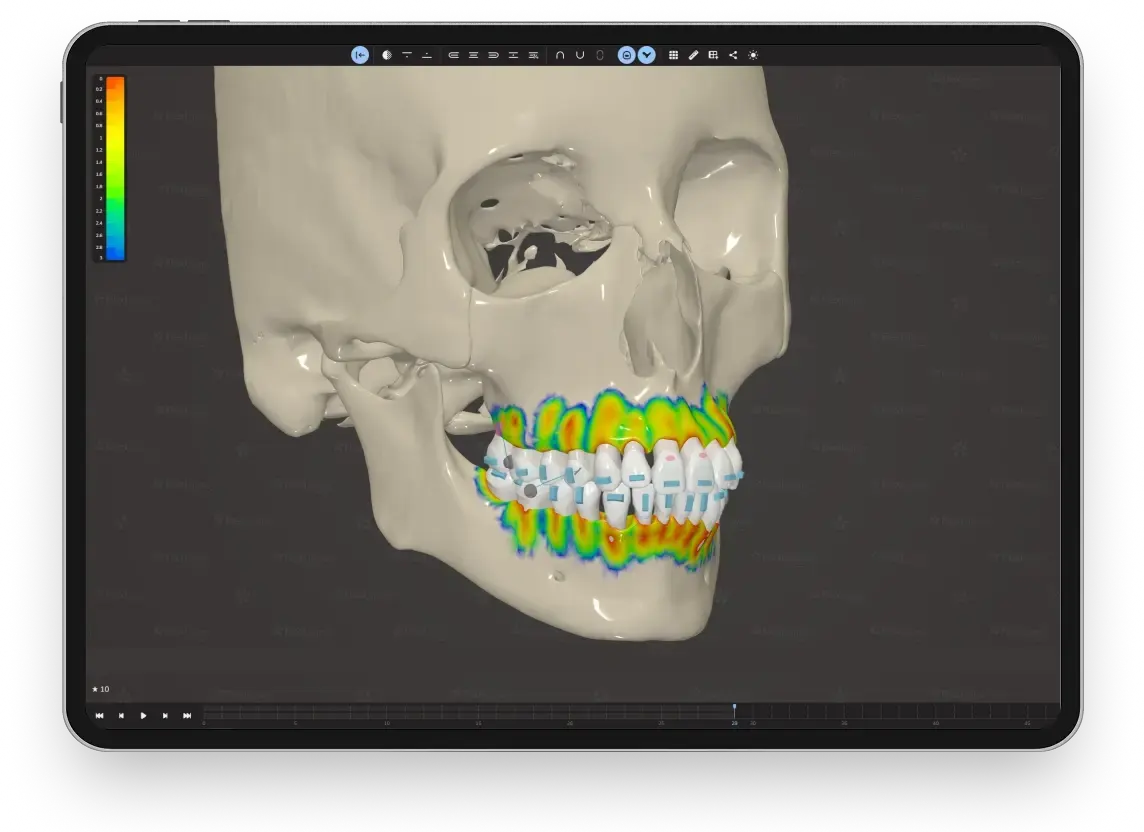

Абсолютный контроль над каждым миллиметром движения зубов и суставов — точная диагностика и уверенное планирование в мире элайнеров.

Наши эксперты помогают в протоколах лечения сложных клинических случаев, включая патологии ВНЧС.

Система FlexiLigner подходит для лечения разной степени деформации — от легкого выравнивания до комплексной коррекции прикуса и работы с височно-нижнечелюстным суставом. Если говорить о доказательной базе, ключевым фактором является не сам диагноз, а грамотный отбор случая и соблюдение протокола. В лёгких и средних случаях результат сопоставим с брекетами, а в сложных ситуациях часто требуется усиленная механика и жесткий контроль результата.